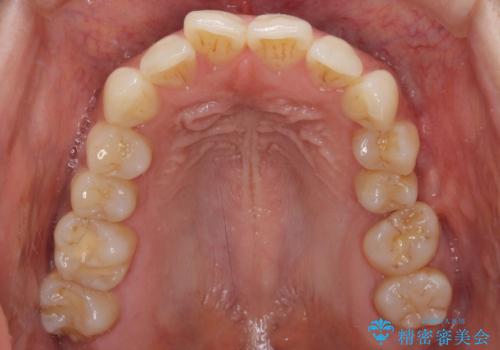

幾度も詰め物治療を行ったため継ぎ接ぎだらけとなっていたため、インレーにて修復治療をすることとしました。

咬合力が強いため、ゴールド合金(PGA)のインレーを選択することとしました。

ゴールドインレーは銀歯のインレーやセラミックインレーと比べ、「技工操作の精度が高く、適合が著しく良い」というメリットがあります。特に上の奥歯は歯科医師の操作が行いにくいため、「適合の良さ」は再治療のリスクを防ぐ上でとても重要な要素となります。

上の奥歯は金属色が見えることもないため、審美的な問題は全くありません。